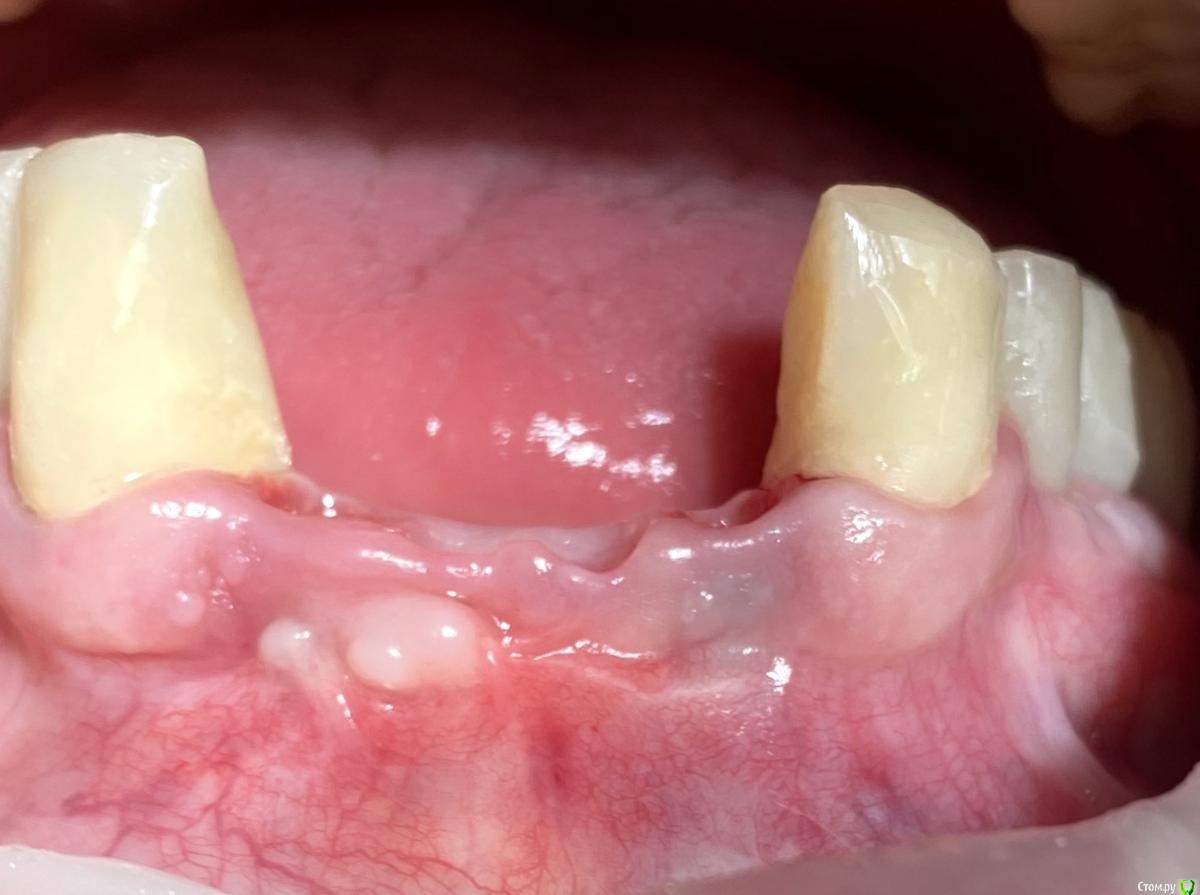

Irouil Опубликовано 4 февраля, 2021 Поделиться Опубликовано 4 февраля, 2021 (изменено) я так понимаю на первой фотке проблема была в толстой поддесневой части. жаль промежуточных этапов не скинули.Фотки тут для примера результата через неделю после использования описанного метода, никаких особо этапов - во время самой хирургии я не фотографирую, к сожалению. Истончать тут для того, чтобы хватило места для питающей ножки - если коронка будет слишком толстая у основания, то она передавит лоскут крестально, ведь в лоскуте посередине перфорация через которую коронка фиксируется к импланту по типу "шашлыка"-пончо. А если интересна проблема, то она в расстоянии от платформы до зенита (на втором фото) порядка 7 мм. И тут уже была неудачная попытка что-то сделать, судя по всему - как раз натянуть коронарный лоскут.странно что никто коронально смещенный не поддержал. разные варианты предложилиА в чем преимущества, на Ваш взгляд? Как мне кажется, в Вашем кейсе с апикального направления тянуть далеко, прикрепленки не безгранично, риски потерять то, что есть - высокие. А сосочки совсем рядом, причем отличные по всем параметрам. Изменено 4 февраля, 2021 пользователем Irouil Ссылка на комментарий

Doctor Vlad Опубликовано 4 февраля, 2021 Автор Поделиться Опубликовано 4 февраля, 2021 ИСТОНЧААААААААТЬ!!!!11 я так понимаю на первой фотке проблема была в толстой поддесневой части. жаль промежуточных этапов не скинули. По картинке проще понять как делать. странно что никто коронально смещенный не поддержал. разные варианты предложили Ссылка на комментарий